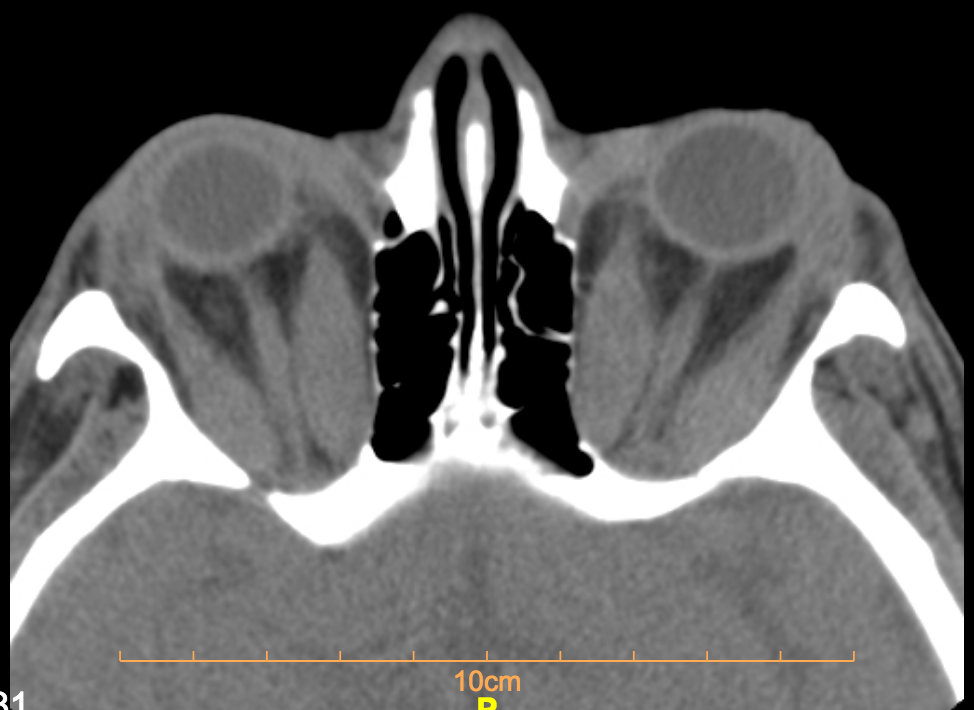

Huge fusiform enlargement of medial and lateral rectus muscles.